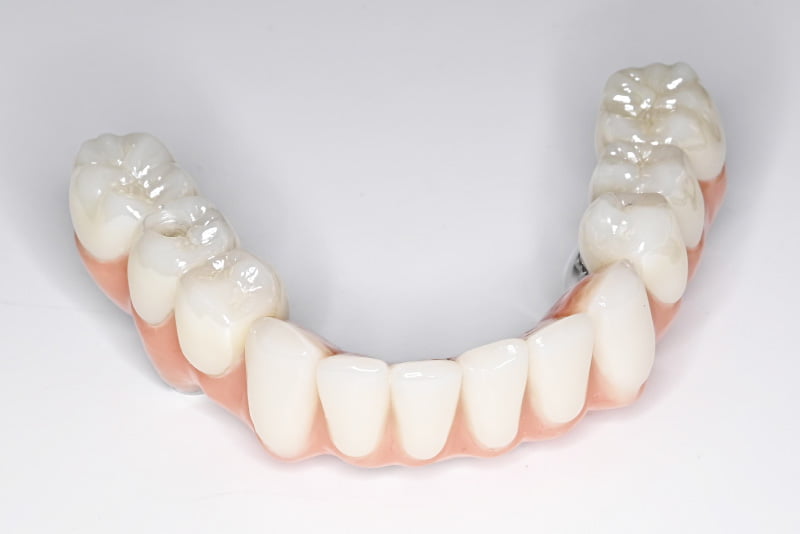

自然で美しい見た目を実現

オールオン4は、ただ噛めるだけでなく、見た目の美しさ(審美性)にも優れた治療です。

入れ歯のように外れたり不自然に見えることがなく、自分の歯のように自然な仕上がりになります。さらに、オールオン4は歯肉の部分も覆うため、普通のインプラントに比べて歯ぐきのラインが整いやすく、より自然で美しい口元を実現できるのも特徴です。

また、被せ物の種類を選ぶことができるため、予算と見た目のバランスを考えて治療を進めることが可能です。